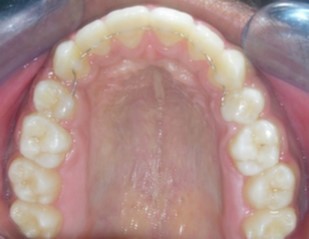

Intraoral assessment. (Figure 1d,Figure 1e,Figure 1f,Figure 1g,Figure 1h).

Figure 1g.Pre-treatment intra-oral-Upper occlusal

The maxillary arch was V-shaped with severely proclined and rotated maxillary incisors with a palatally placed 12. The mandibular arch was U-shaped with severe crowding of mandibular incisors, with 43 partially erupted and buccally placed with transpositioned 42 and 43, with 42 mesiolingually rotated, 33 distolingually rotated and 34 distolingually rotated and buccally placed.

Severe increase in overjet and deep bite were both observed. The maxillary midline coincided with the skeletal midline but the mandibular midline was shifted to the right side by 1 mm. Bilateral maxillary posterior crossbite was also observed. On right side the molar relation was Class I and on the left side it was Class II. The canine relation was Class II on the left side and the curve of Spee was increased.